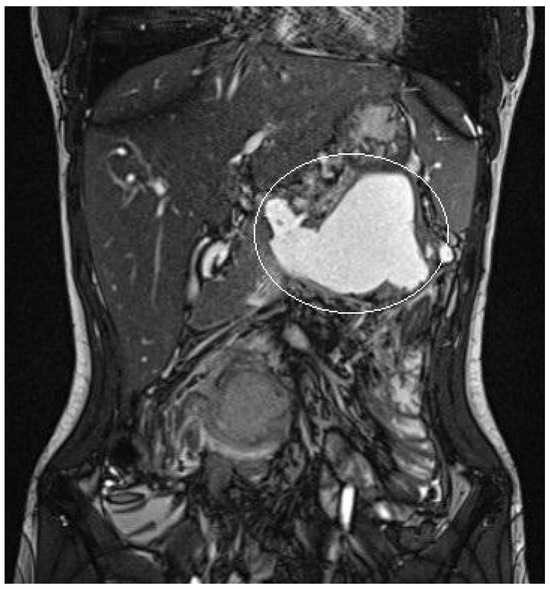

3.1.3. Patient n°3

A 10-year boy affected by T-lymphoblastic lymphoma developed a WON after chemotherapy-induced necrotic-hemorrhagic pancreatitis, with fever, vomit and abdominal pain. Clinical conditions were also complicated by deep vein thrombosis involving the left femoral vein and inferior vena cava. Abdominal CT showed a large WON, with a major diameter more than 22 cm (Figure 5). Considering the worsening of clinical condition and the need to an early resume of the chemotherapy, he underwent a primary EUS-guided cystogastrostomy and EC-LAMS positioning; we did not perform necrosectomy. Post-operative course was uneventful. MRI performed 37 days after the procedure, showed a significant reduction of the WON (Figure 6); subsequent US images were performed for follow-up, until the WON was no more visible. Endoscopic removal of the device was performed 48 days after cystogastrostomy.

Figure 6.

Patient n°3 MRI. Reduction of the walled-off necrosis; the device is in place (in the white circle).

Patient is still undergoing oncologic therapy, but at one-year follow-up he has had no recurrence of acute pancreatitis and PFCs.